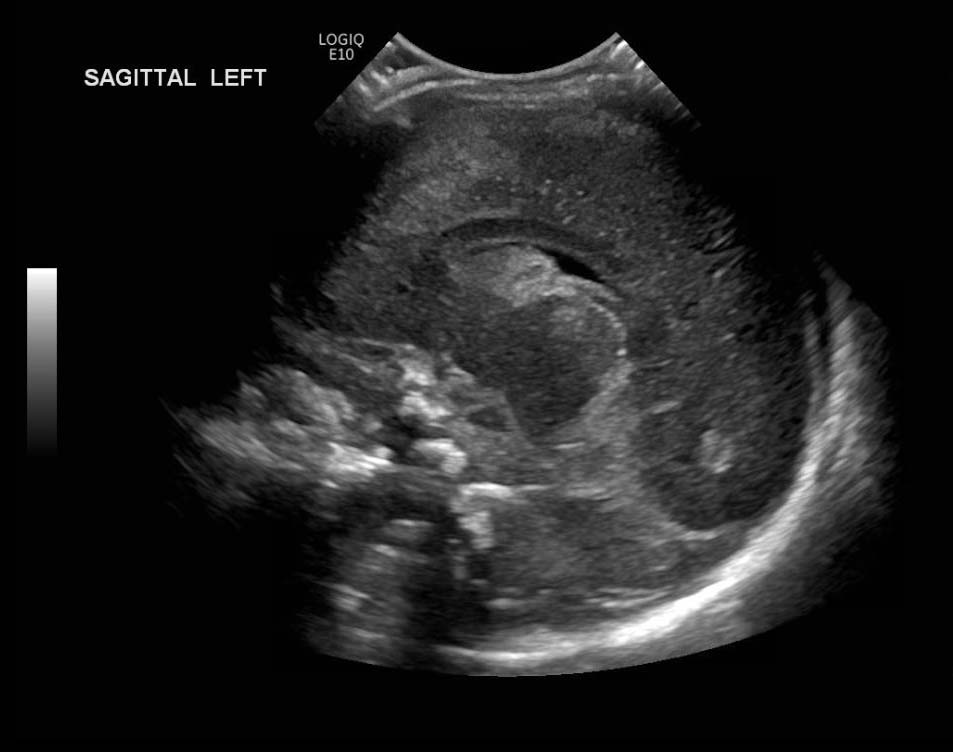

Age: 4 days (born at 24 weeks)

Sex: Male

Indication: Evaluate for germinal matrix hemorrhage

Grade 2 germinal matrix hemorrhage

Sample ReportLeft germinal matrix hemorrhage involving the caudothalamic groove and layering in the occipital horn of the left lateral ventricle without hydrocephalus (grade 2).

No abnormal brain parenchymal echogenicity or extra-axial collections.

Premature sulcation pattern.